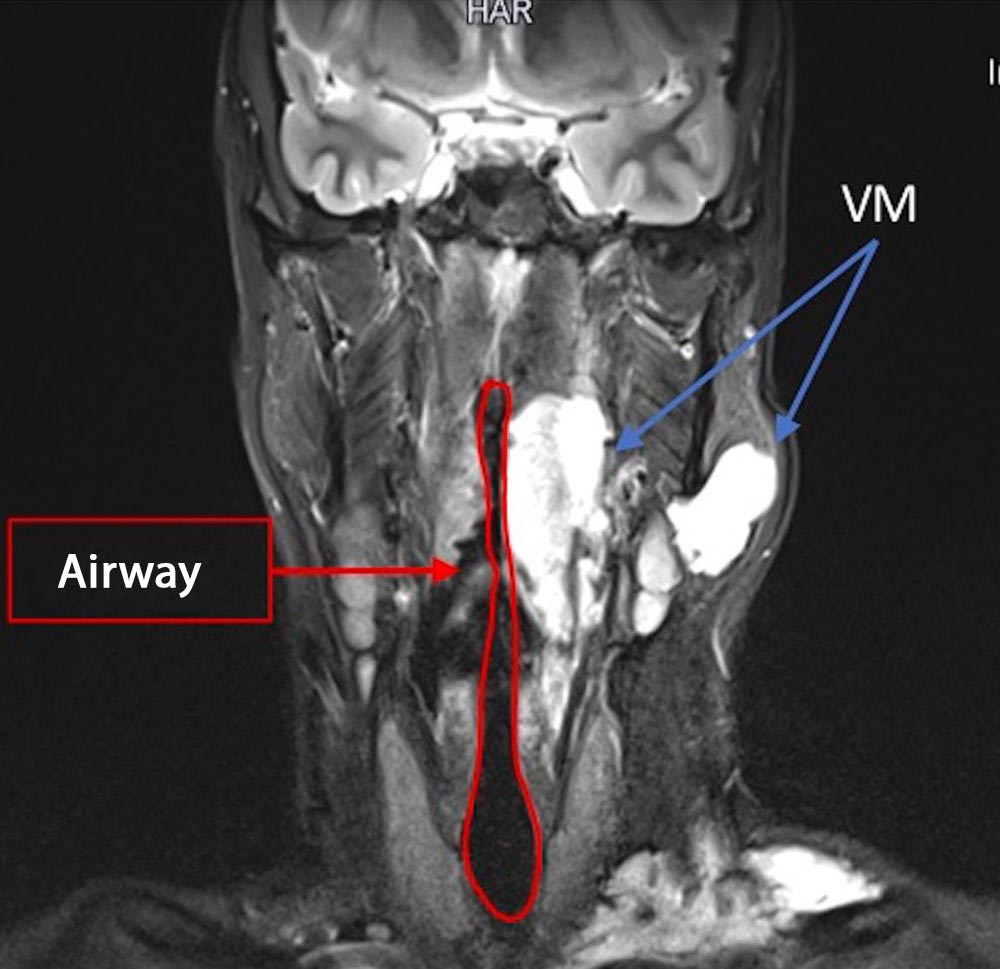

• Male patient aged 24 years.

• There is a voluminous venous malformation in the neck.

• The malformation extends into the piriform sinus and the glottic plane (hypopharynx).